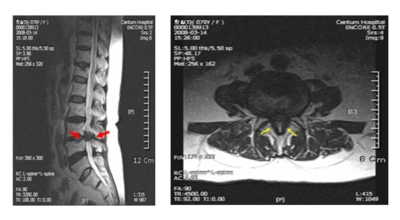

요추관 협착증은 척추 내 신경이 지나가는 통로가 좁아지는 현상으로 기인해서 신경이 눌리면서 이에 따른 여러가지 증상을 유발하는 질환을 의미해요.

허리 협착증은 척추관이 좁아지게 되면서 신경을 압박하게 되어 허리통증과 또한 다리에도 여러가지 증상을 일으키게 되는데, 발생 원인은 주로 노화로 인한 퇴행성 변화가 많았지만 요즈음는 옳지 않은 자세로 오랫동안 앉아있는 사람들이 많아지면서 생기는 경우도 많아졌으며, 선천적인 요인으로 나타나는 경우도 있답니다.

일상생활에서 허리 척추에 무리를 주는 행위가 반복적으로 행해질 경우 허리 뿐만 아니라 주변 근육과 인대의 퇴행이 빨라질 수 밖에 없어요. 허리 협착증의 경우 허리를 뒤로 젖히면 통증이 심하게 나타나지만 허리를 굽히면 척추관이 일시적으로 넓어지는 영향으로 통증이 줄기 때문에 자연스럽게 아프지 않은 자세를 하다보니 허리가 점점 굽는 자세를 만들 수 있어요.